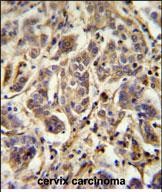

- FLJ11506 Antibody (C-term) (Cat. #P30687) immunohistochemistry analysis in formalin fixed and paraffin embedded human cervix carcinoma followed by peroxidase conjugation of the secondary antibody and DAB staining. This data demonstrates the use of the FLJ11506 Antibody (C-term) for immunohistochemistry. Clinical relevance has not been evaluated.